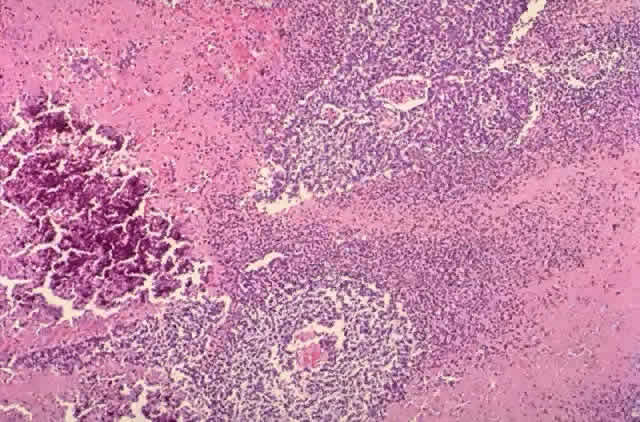

Tumor rosettes were described by Flexner91 in 1881 and Wintersteiner92 in 1897. Multinucleated tumor cells probably represent regression.93 Flexner-Wintersteiner and Homer-Wright rosettes may be seen (Figs. 5 and 6). Flexner-Wintersteiner rosettes are lined with cuboidal cells that have terminal bars at the apical ends, creating a central lumen. These represent an attempt at retinal differentiation set in a field of undifferentiated cells. Homer-Wright rosettes are less characteristic of retinoblastoma. They are associated with medulloblastoma. The cells are arranged around a central tangle of cytoplasmic processes. “Fleurettes” represent a higher degree of maturation. The cells demonstrate evidence of photoreceptor differentiation in small, bouquet-like clusters (Fig. 7). Cell differentiation with fleurettes and FlexnerWintersteiner rosettes may have a better prognosis.52,94 The hereditary variant of retinoblastoma has been shown to be more highly differentiated.95

Fig. 6. Homer-Wright rosette (H & E, × 100).